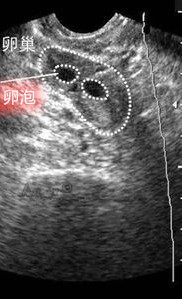

阴道超声测卵泡

什么时候检测排卵时间呢?一般对未使用促排卵药物的女性,建议在月经的第10天开始;使用了促排卵药物的女性,在使用刺激药物后的第 5~6 天复诊监测卵泡,评价卵巢对促排卵药物反应情况,判断是否加用 HMG 或其他辅助用药。之后按照卵泡的生长规律继续进行阴道超声监测,一般卵泡生长速度在直径 14 mm 前每天增加 1~1.5 mm,从直径 14 mm 开始卵泡生长加快,每天增长 2~3 mm 。当卵泡直径 ≥ 14 mm,让男方排精 1 次 (以便排卵日同房具有较佳精子质量),并隔天或者每天复诊阴道超声测量卵泡大小。最后结合内膜、卵泡情况,确定使用 hCG 时机。当卵泡直径 18 mm 以上,内膜 8 mm 以上时可考虑注射 hCG 5000~10000 IU,注射后 36 小时 排卵,安排适时同房,同房次日复诊阴道超声评估是否卵泡破裂。